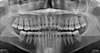

• une radiographie panoramique